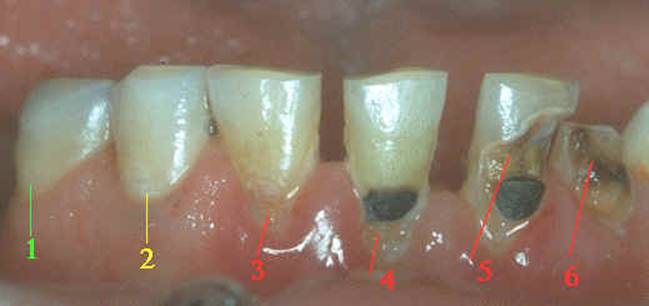

La caries dental es una desmineralización de la superficie

del diente causada por bacterias, que se adhieren a la superficie dental. En

la fotografía se observan las distintas etapas de dicha desmineralización en

superficies lisas:

Superficie dental sin caries.

Los primeros signos de desmineralización, es una

mancha blanca. No es aún una cavidad, la superficie es todavía uniforme. Con

medidas apropiadas, (las aplicaciones de flúor

realizadas por el profesional y la indicación de usar una pasta con

alto contenido de flúor) el proceso de caries

puede ser parado aquí.

La superficie de esmalte se ha estropeado. Ahora es

una caries dental superficial de fácil restauración por el profesional.

Una obturación o relleno ha sido hecho, pero como se

puede ver, el proceso de desmineralización a continuado y la lesión

de caries rodea el relleno. Esto se llama Caries

Secundaria; pero de hecho, esto es por lo general, la misma enfermedad que

está en progreso.

La desmineralización

continúa y destruye la pieza dental infectando al órgano pulpar más conocido

como nervio.

Si el proceso continúa se produce la fractura de la

pieza dental.